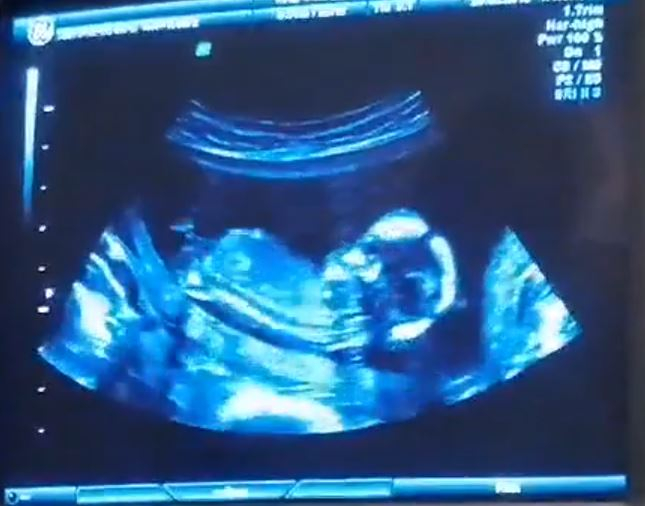

Мальчик или девочка? Помогите разглядеть))

Пол малышаНу вот, сходила сегодня на узи. Срок: примерно 13недель и 5 дней. Думала что уж сегодня наверняка сделают предположение о поле малыша. Так узистка сказала что еще рано, и на следующем узи уж точно увидят. Но мне всё равно ужасно интересно кто же у меня там сидит))) Девченки, вот ниже снимки с видео, мне показалось что на первом снимке девочка, а на остальных вроде мальчик. А вы что видете?))))

Девочки, кто сказал мальчик-вы оказались правы)) Сегодня получила результаты анализа крови-обещают мальчика)) Спасибо всем))